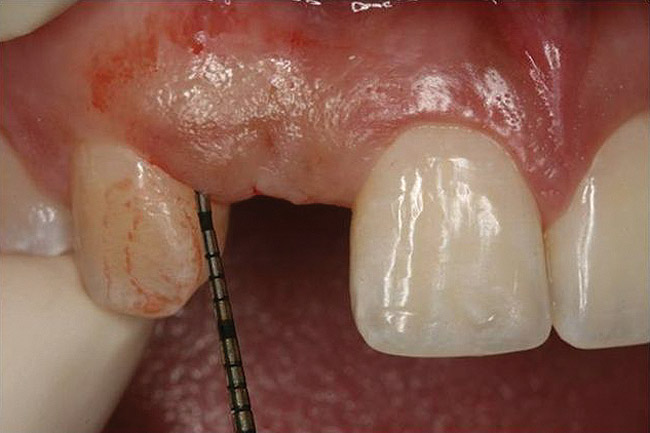

Figure 4  Characterization of the interproximal bone and tooth contacts: A periapical radiograph assists in measuring the distance from bone crest to the adjacent tooth contact points for missing tooth No. 8. The mesial bone crest to the adjacent tooth contact distance is < 5 mm, while the distal bone crest to adjacent tooth contact distance is > 6 mm (Fig 4). One-year following implant placement, conservation of these dimensions is revealed (Fig 5). The clinical photograph (Fig 6) of the lateral incisor adjacent to tooth No. 8 implant crown demonstrates that the absence of distal interproximal (papilla) fill related to the observed bone crest to contact distance exceeds 6 mm.

Figure 6  Characterization of the interproximal bone and tooth contacts: A periapical radiograph assists in measuring the distance from bone crest to the adjacent tooth contact points for missing tooth No. 8. The mesial bone crest to the adjacent tooth contact distance is < 5 mm, while the distal bone crest to adjacent tooth contact distance is > 6 mm (Fig 4). One-year following implant placement, conservation of these dimensions is revealed (Fig 5). The clinical photograph (Fig 6) of the lateral incisor adjacent to tooth No. 8 implant crown demonstrates that the absence of distal interproximal (papilla) fill related to the observed bone crest to contact distance exceeds 6 mm.

Figure 6